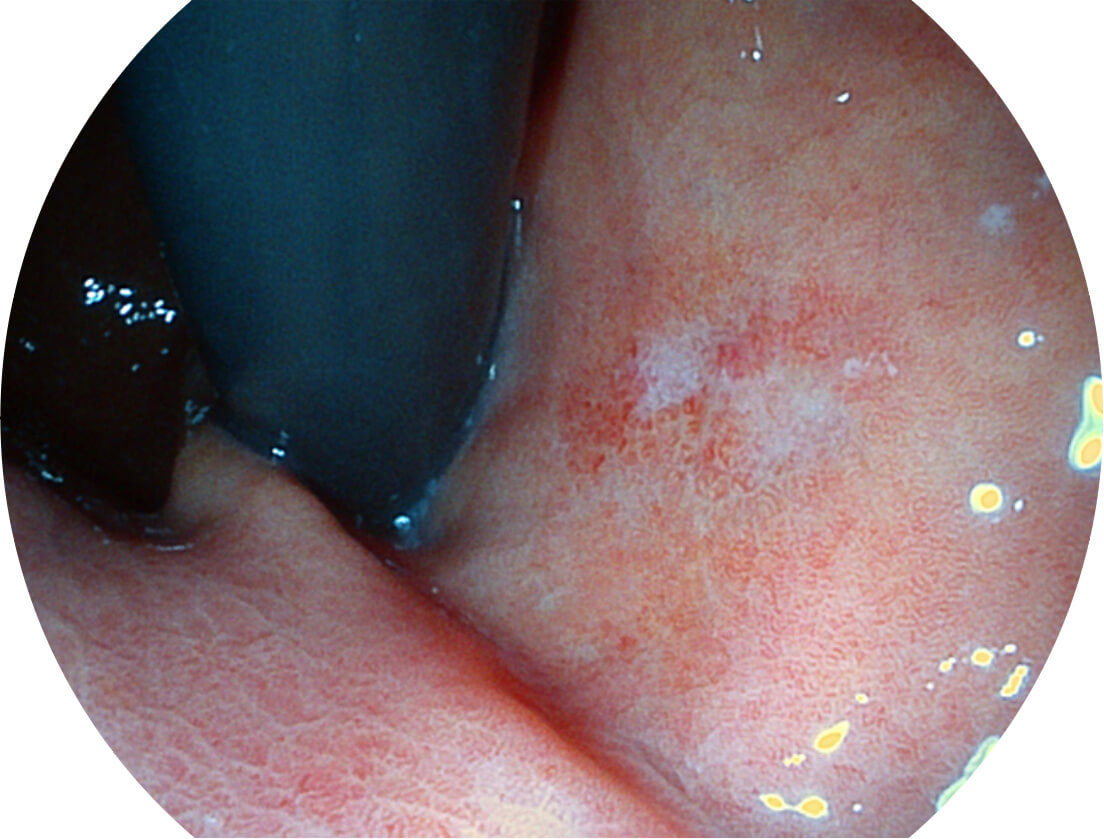

白光图像

SFI图像

强调浅层黏膜结构的同时,保证照明亮度和提升浅层微血管与中层血管颜色对比度,病变边界更清晰。

采用光路合束技术,光谱自由度高,实现了更丰富的照明模式,染色模式SFI及VIST,从远景到近景,助力消化道早期疾病诊断。